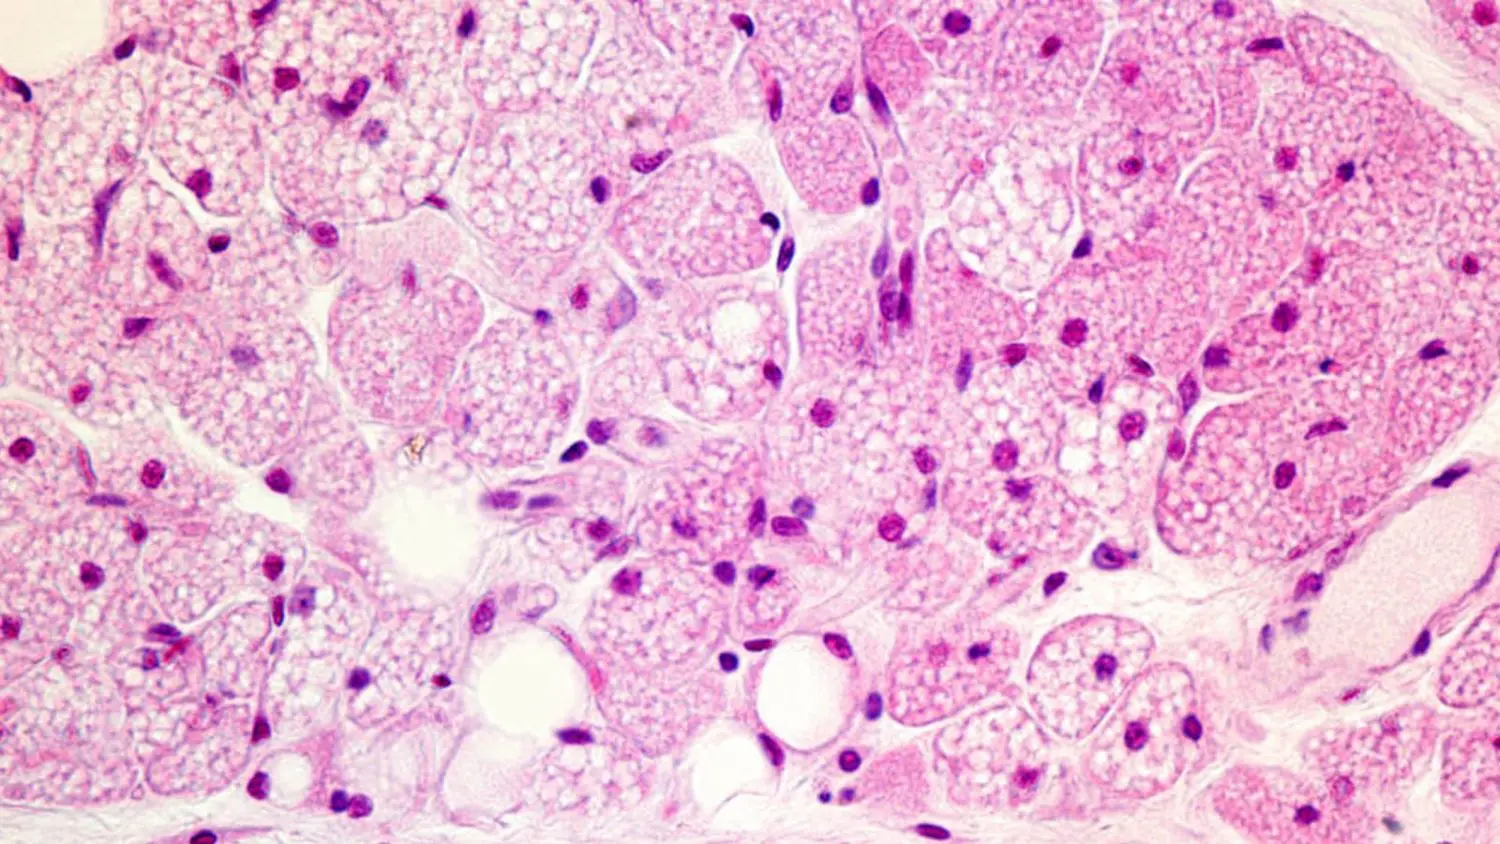

Los investigadores han demostrado que la grasa parda está compuesta por células con una alta cantidad de mitocondrias, los «motores» de las células que generan energía. Estas mitocondrias contienen una proteína única, la termogenina, que permite a la grasa parda convertir la energía alimentaria directamente en calor. Este proceso no solo ayuda a regular la temperatura corporal sino que también podría ser clave en la regulación del peso corporal y el metabolismo.